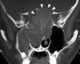

Intracranial tumor with erosion

Pott's puffy tumor, first described by Sir Percivall Pott in 1760, is a rare clinical entity characterized by subperiosteal abscess associated with osteomyelitis. It is characterized by an osteomyelitis of the frontal bone, either direct or through haematogenic spread. [Source: Wikipedia ]